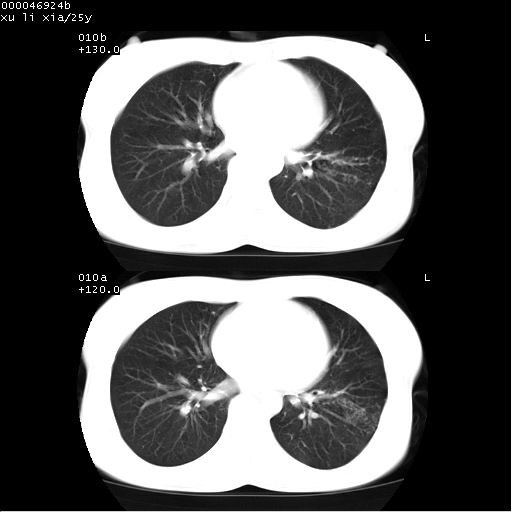

患者 女,25岁。因“左侧卵巢肿瘤”术前胸片偶然发现两肺病变。平素无明显不适,无呼吸系统症状及体征,无传染病史。

cr x线胸片提示:两肺感染性病变(结核可能性大)。

胸部ct轴位平扫(层厚10mm,螺距1.5,重建间隔10mm),图像如下:

(注:上级医院会诊胸部ct片——考虑为肺部真菌感染。)

病灶呈地图样分布于肺外围,与正常组织分界清晰+弥漫性磨玻璃影中见小叶间隔增厚呈碎石路样表现+年轻女性,无明显临床症状=肺泡蛋白沉积症?